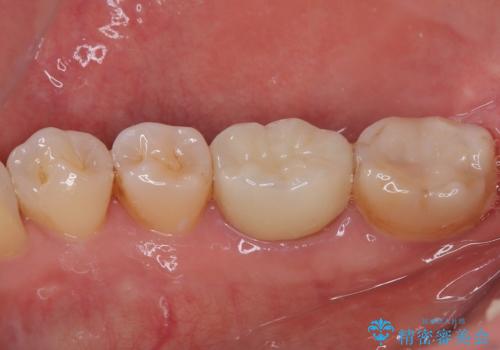

- 当院で矯正後に銀歯が目立つのでやり替えたいと来院された患者様です。銀色の詰め物(メタルインレー)と歯の間に隙間を認め、あまり歯を削りたくないとのことで患者様と相談の結果右下の7番目の歯はセラミックインレー、右下の6番目の歯はメタルインレーが大きいためフルジルコニアクラウンでの治療を行うことになりました。

拡大鏡視野下で、銀色の詰め物(メタルインレー)、保険のプラスチック、虫歯の除去を行い、セラミックインレー、フルジルコニアクラウンに適した形に整えました。

歯と歯茎の間に圧排糸と言われる糸を入れてシリコーン印象材にて精密な型どりをしました。

セラミックインレーの装着時には、唾液の侵入を防ぐために、ラバーダム防湿を行いました。

特に異常もなく見た目、噛み合わせともに満足していただけました。